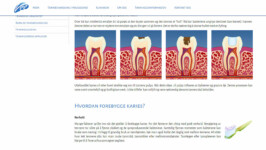

Dental Web har per i dag informasjon om over 60 ulike emner, fordelt på 15 hovedkategorier (se egen oversikt). Den faglige informasjonen er lettfattelig og suppleres med tydelige illustrasjoner og kliniske fotografier. Nåværende versjon av Dental Web har hovedfokus på tannpleierens og allmenntannlegens arbeidsoppgaver, men på sikt vil vi supplere med informasjonsmoduler som også retter seg mot ulike spesialiteter.